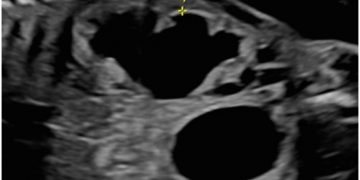

Cari soci, finalmente online le soluzioni dei casi del mese di Luglio Grazie a Carlotta Zorzi e Daniele Di Mascio!! Caso 1 - video [pdf-embedder url="https://www.sieog.it/wp-content/uploads/2024/07/risposta-Casodelmese_Luglio20241.pdf" title="risposta...